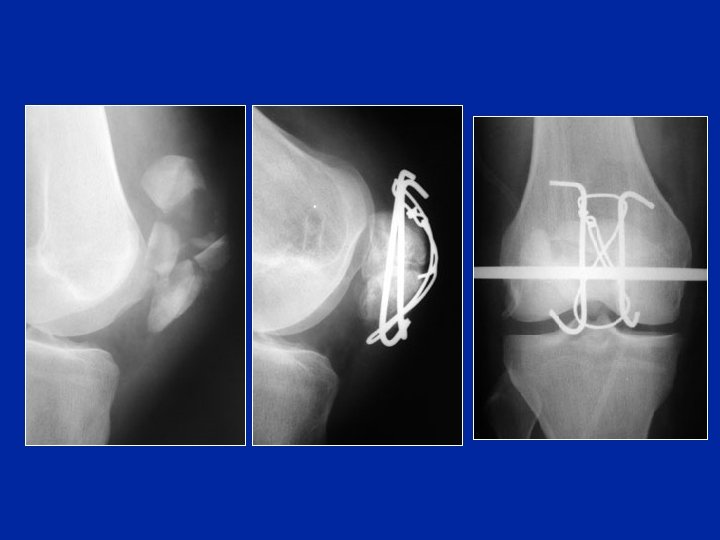

Tecnica con hauban Vite semplice

Trattamento delle fratture di rotula Hauban corretto Pessimo cerchiaggio

Tirante + cerchiaggio

Quali tratamenti proponete ai soggetti di 20 anni, per una frattura di rotula ? 1/ trasversale non scomposta : 2/ trasversale molto scomposta : 3/ trasversale molto scomposta e esposta : – 1 : gesso inguino malleolare in estensione per 4 settimane, appoggio e rieducazione graduale. – 2 : osteosintesi con la tecnica dell’hauban e mobilizzazione attiva graduale e precoce. Doccia amovibile. – 3 : osteosintesi con la tecnica dell’hauban e disinfezione, lavaggio, sutura, drenaggio, trattamento antibiotico e prevenzione del tetano.